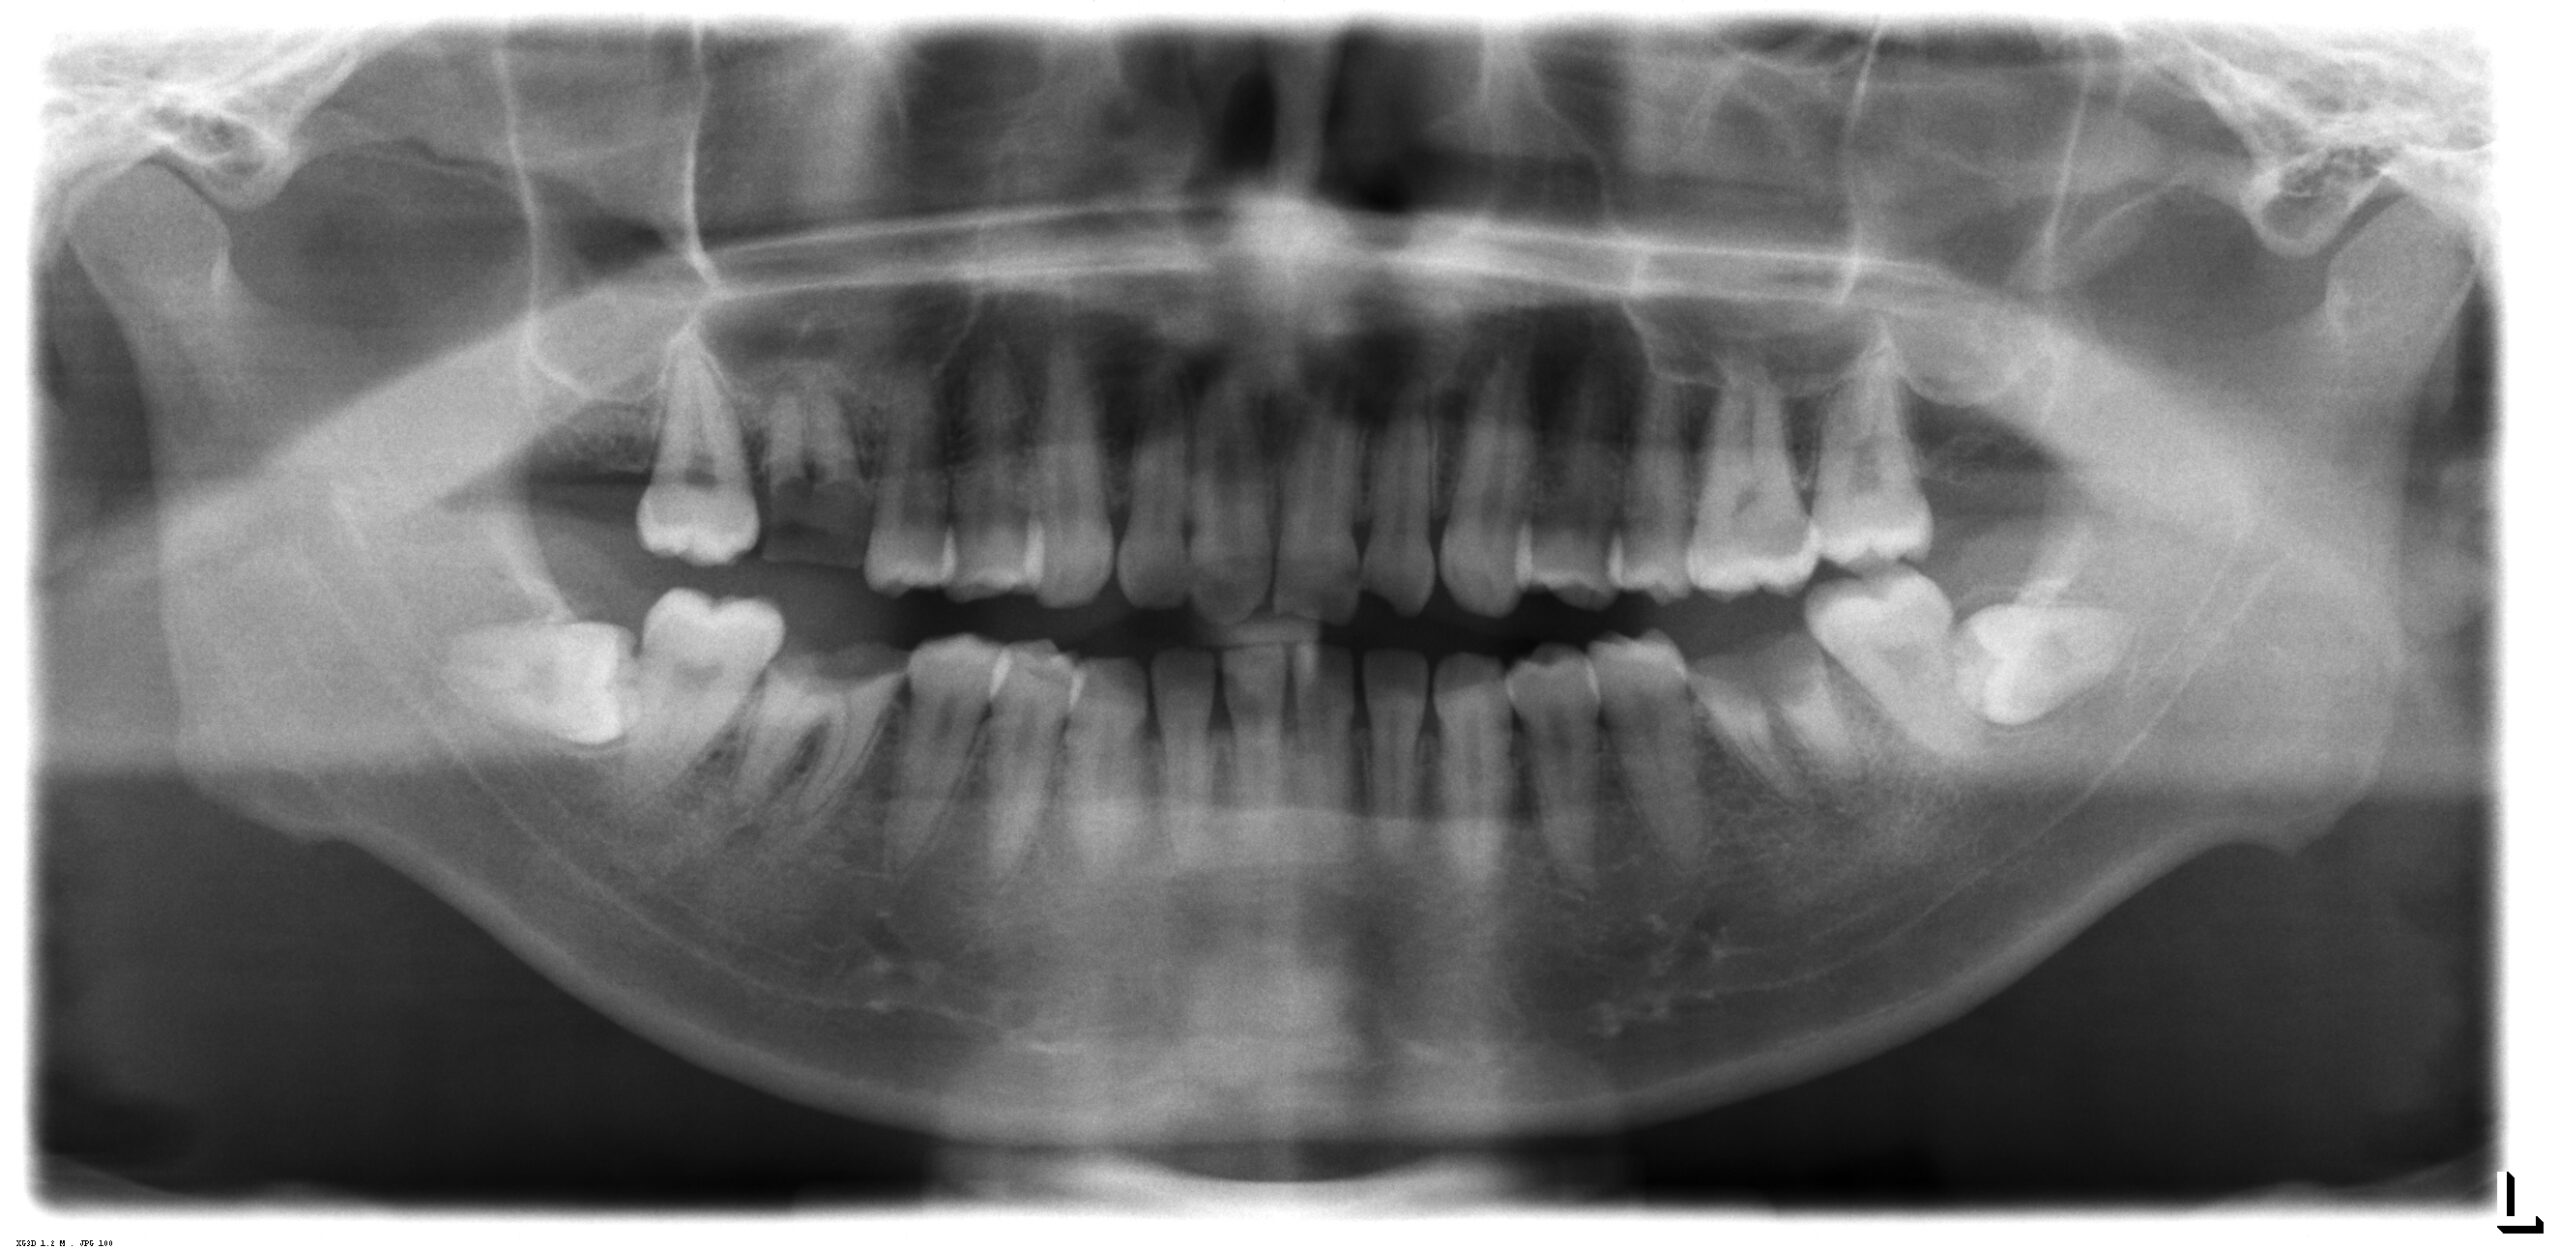

術前のレントゲン写真です。3か所の歯が抜歯となります。